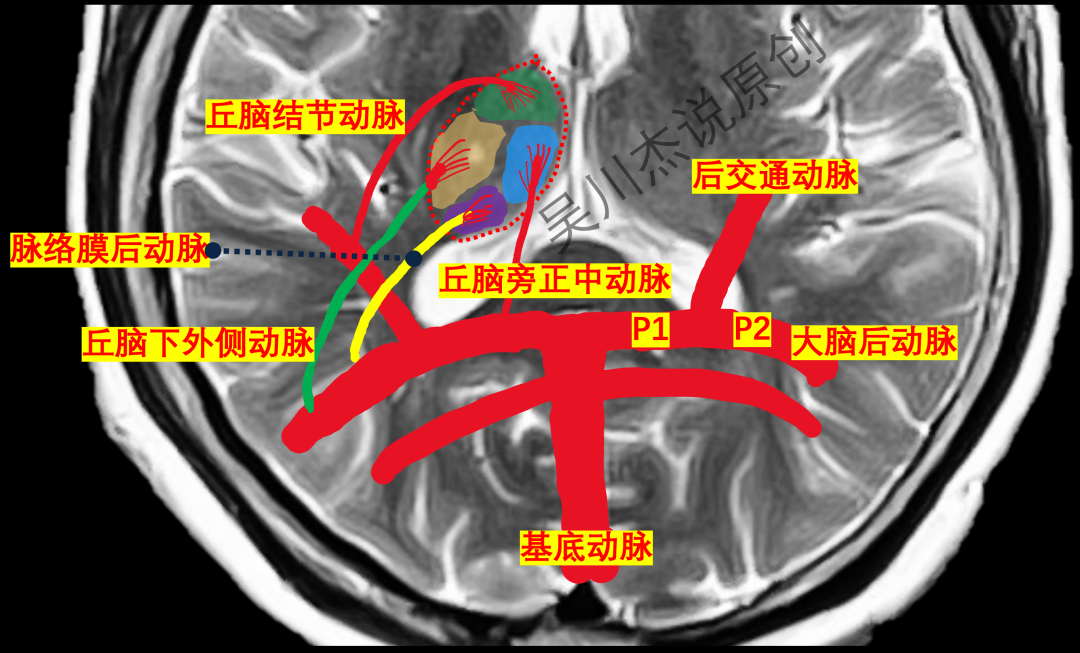

上面的图片单击可以放大查看,仔细看看,丘脑主要的血供有4个

• 丘脑结节动脉:又称极动脉,起自后交通动脉。其实极动脉更为形象,从上图看,这根动脉供应丘脑的大概北极的部位。

• 丘脑旁正中动脉:又称丘脑穿通动脉,起自大脑后动脉P1段。很多书上习惯用丘脑穿通动脉,我更喜欢旁正中动脉。很简单,这根动脉供应丘脑靠近中线的旁边。

• 丘脑下外侧动脉:又称丘脑膝状体动脉,起自大脑后动脉P2段。朋友们,抛弃这个难以记忆的丘脑膝状体动脉的称呼,丘脑下外侧动脉当然是供应丘脑的下外侧部分了。

• 脉络膜后动脉:起自大脑后动脉P2段。貌似最后丘脑大概南极位置的血供就只剩下脉络膜后动脉来供应了吧。

放大一点,我们再来看看上图中这4根动脉的供血范围。

下面是一个平面的模式图。

我们再来看看一个立体的模式图,从另外一个角度再来理解一下这四根动脉的起源、走形和分布。